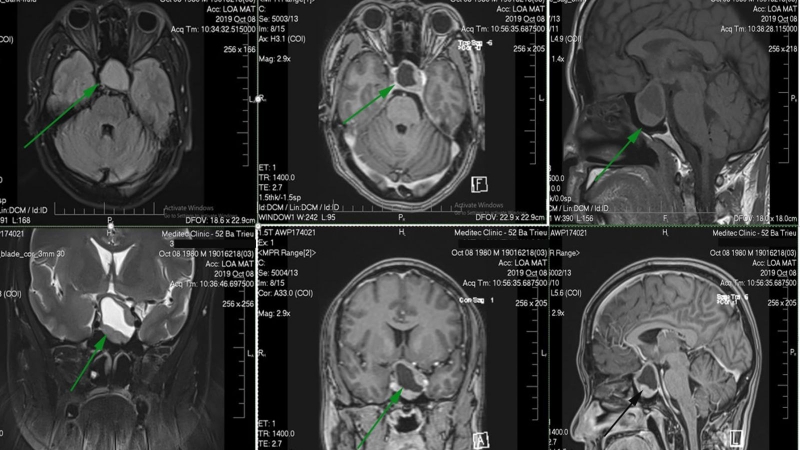

Chụp MRI cần chuẩn bị gì khi có thuốc đối quang từ?-1 Chụp MRI cho hình ảnh sắc nét giúp bác sĩ chẩn đoán tốt hơn.

Chụp MRI cần chuẩn bị gì khi có thuốc đối quang từ?-2 Chụp MRI cần chuẩn bị gì khi có thuốc đối quang từ?